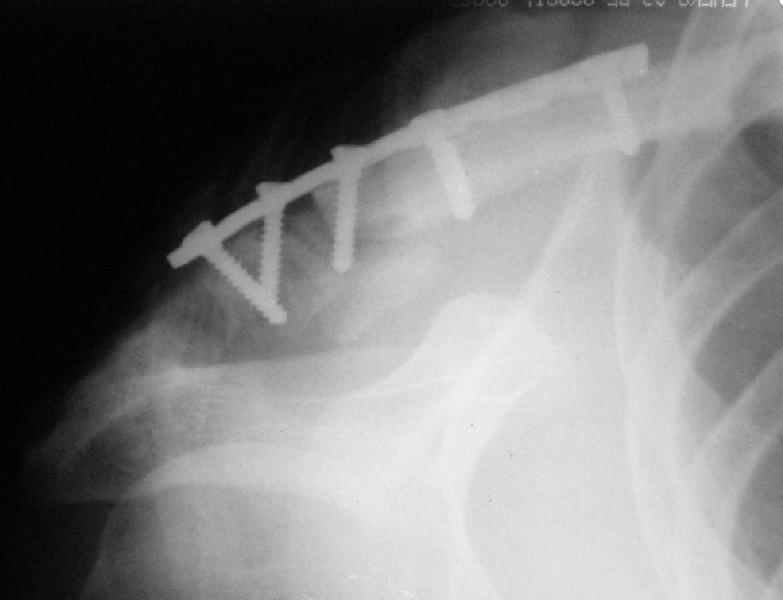

Сегодня прооперировал больного - накостный остеосинтез реконструктивной пластиной с ааллотендопластикой кл-кл связки.

На операции - обширная межотломковая ткань - мобилизовал проксимальный отломок без иссечения м-отломк.ткани, резекция выступающего конца( в последующем использовал как трансплантат).

Однако, я сомневаюсь в правильности выбора метода фиксации - фактически только 1 винт (на акромиальном отростке) является рабочим и мне кажется зря вы не убрали рубцы из зоны перелома - для костного сращения контакт кость-кость вроде бы как желателен.

После мобилизации проксимального отломка достигнут контакт в нижней части . 2 винта в дистальном отломке + петля аллосухожилия, проведенная через канал в проксимальном отломке должна нейтрализовать смещающие силы - надеюсь.